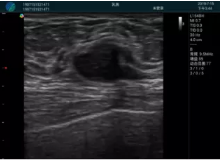

清晰顯示腺體內(nèi)低回聲快影,邊界清晰,包膜較光滑

確定進針路徑并實時監(jiān)測抽吸針與腫塊位置關(guān)系

抽吸針進入腫塊內(nèi)部進行旋切

抽吸過程中可見腫塊明顯縮小,并根據(jù)腫塊位置改變針道位置

抽吸旋切后再進行超聲復(fù)查,原腫塊區(qū)域未見殘留組織及出血